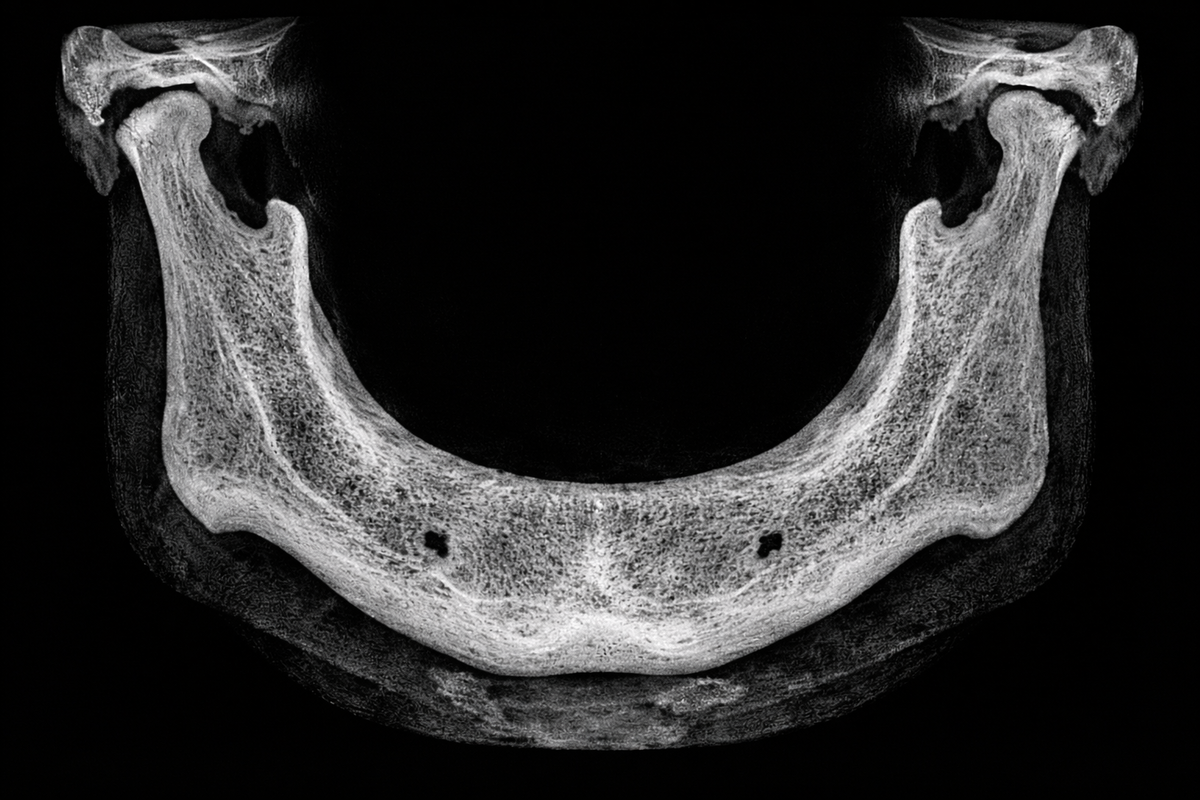

Причина 1. Атрофия кости с возрастом

КТ нижней челюсти

Одна из главных причин — естественная потеря костной ткани.

Если зубы давно удалены, то челюсть постепенно «усыхает» — это называется атрофией.